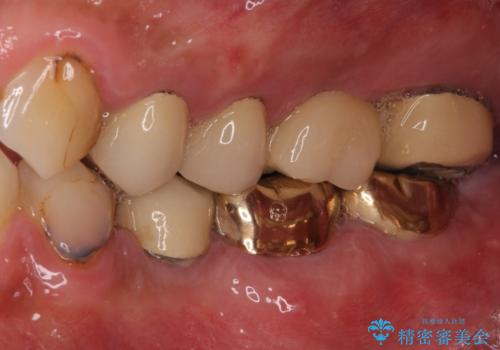

抜歯が必要な左右の奥歯 ブリッジとインプラントによる奥歯の補綴治療

- 咬んだときに奥歯に痛みを感じるとのことで来院された患者様です。

診査の結果、左側は奥歯2本、右側は1本の抜歯が必要であることが分かりました。

左側は大臼歯2本と小臼歯1本が欠損しているため、インプラント2本を治療したブリッジ、右側は中間欠損であり、前後の歯も加療が必要であったためブリッジによる補綴治療を行うこととしました。

抜歯となった歯は全て神経が抜かれた歯であり、強大な咬合力によって破折したことが原因で抜歯となりました。